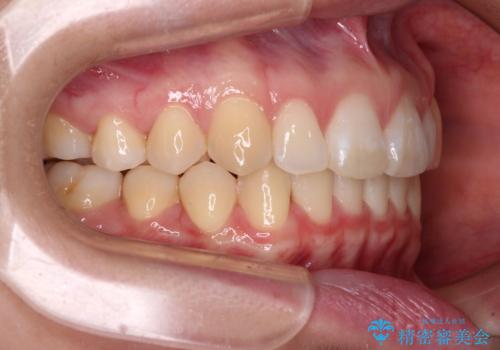

- 上顎前歯の隙間を気にして来院された患者様です。

下顎前歯が上顎前歯に食い込むような咬み合わせにより、上顎前歯が開いてしまっていたため、咬合高径の挙上により突き上げを改善するよう、インビザラインにより矯正治療を行うこととしました。

咬合高径の挙上により上顎前歯の突出感も改善することができ、整った口元となりました。